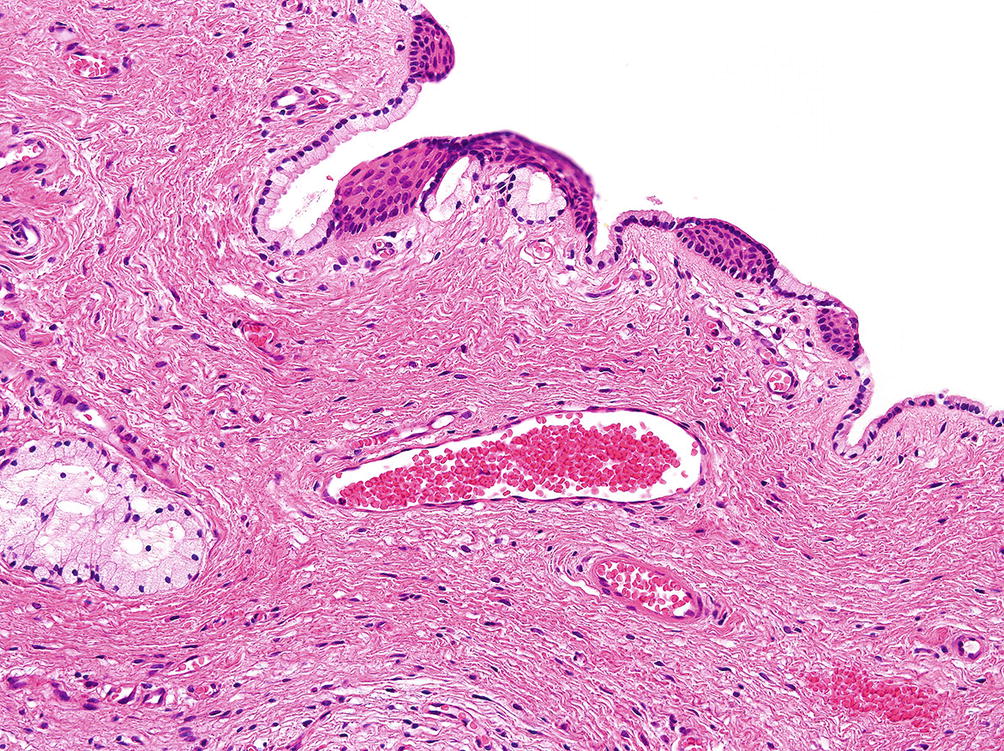

Gartner Duct Cyst Pathology. A collection of surgical pathology images gartner duct cyst. The differential diagnosis between mullerian and gartner s duct cysts requires histochemical evaluation of epithelial mucin production. Benign vaginal cysts are in the majority of cases asymptomatic and are often incidentally discovered during gynecological examination for other purposes. A gartner s duct cyst sometimes incorrectly referred to as vaginal inclusion cyst is a benign vaginal cyst that originates from the gartner s duct which is a vestigial remnant of the mesonephric duct wolffian duct in females.

Gartner s duct cyst cuboidal epithelium. Gartner duct cysts are located in the anterolateral wall of the proximal superior portion of the vagina 2 and are typically located above the level of the most inferior aspect of the pubic symphysis. Müllerian cyst endocervical epithelium. It is a benign cyst that is lined by non secretory cuboidal columnar epithelial cells when observed under a microscope by a pathologist. Aka epidermal inclusion cyst.

These are also known as mesonephric cysts of vagina there are no clearly established risk factors. Gartner s duct cyst cuboidal epithelium. It is a benign cyst that is lined by non secretory cuboidal columnar epithelial cells when observed under a microscope by a pathologist. Uterine tube fallopian tube ovary. A collection of surgical pathology images gartner duct cyst.

The differential diagnosis between mullerian and gartner s duct cysts requires histochemical evaluation of epithelial mucin production. Like other cysts they are lined with non mucinous cuboidal or columnar epithelium. A gartner s duct cyst sometimes incorrectly referred to as vaginal inclusion cyst is a benign vaginal cyst that originates from the gartner s duct which is a vestigial remnant of the mesonephric duct wolffian duct in females. During a routine pelvic exam a 20 year old woman has a 1 cm cystic mass incidentally discovered on the lateral wall of the vagina. Gartner duct cysts are located in the anterolateral wall of the proximal superior portion of the vagina 2 and are typically located above the level of the most inferior aspect of the pubic symphysis.

Bartholin s duct cysts were lined by transitional mucin rich columnar or squamous epithelium and were frequently accompanied by inflammation. Gartner duct cysts are located in the anterolateral wall of the proximal superior portion of the vagina 2 and are typically located above the level of the most inferior aspect of the pubic symphysis. It is a benign cyst that is lined by non secretory cuboidal columnar epithelial cells when observed under a microscope by a pathologist. Like other cysts they are lined with non mucinous cuboidal or columnar epithelium. Aka epidermal inclusion cyst.